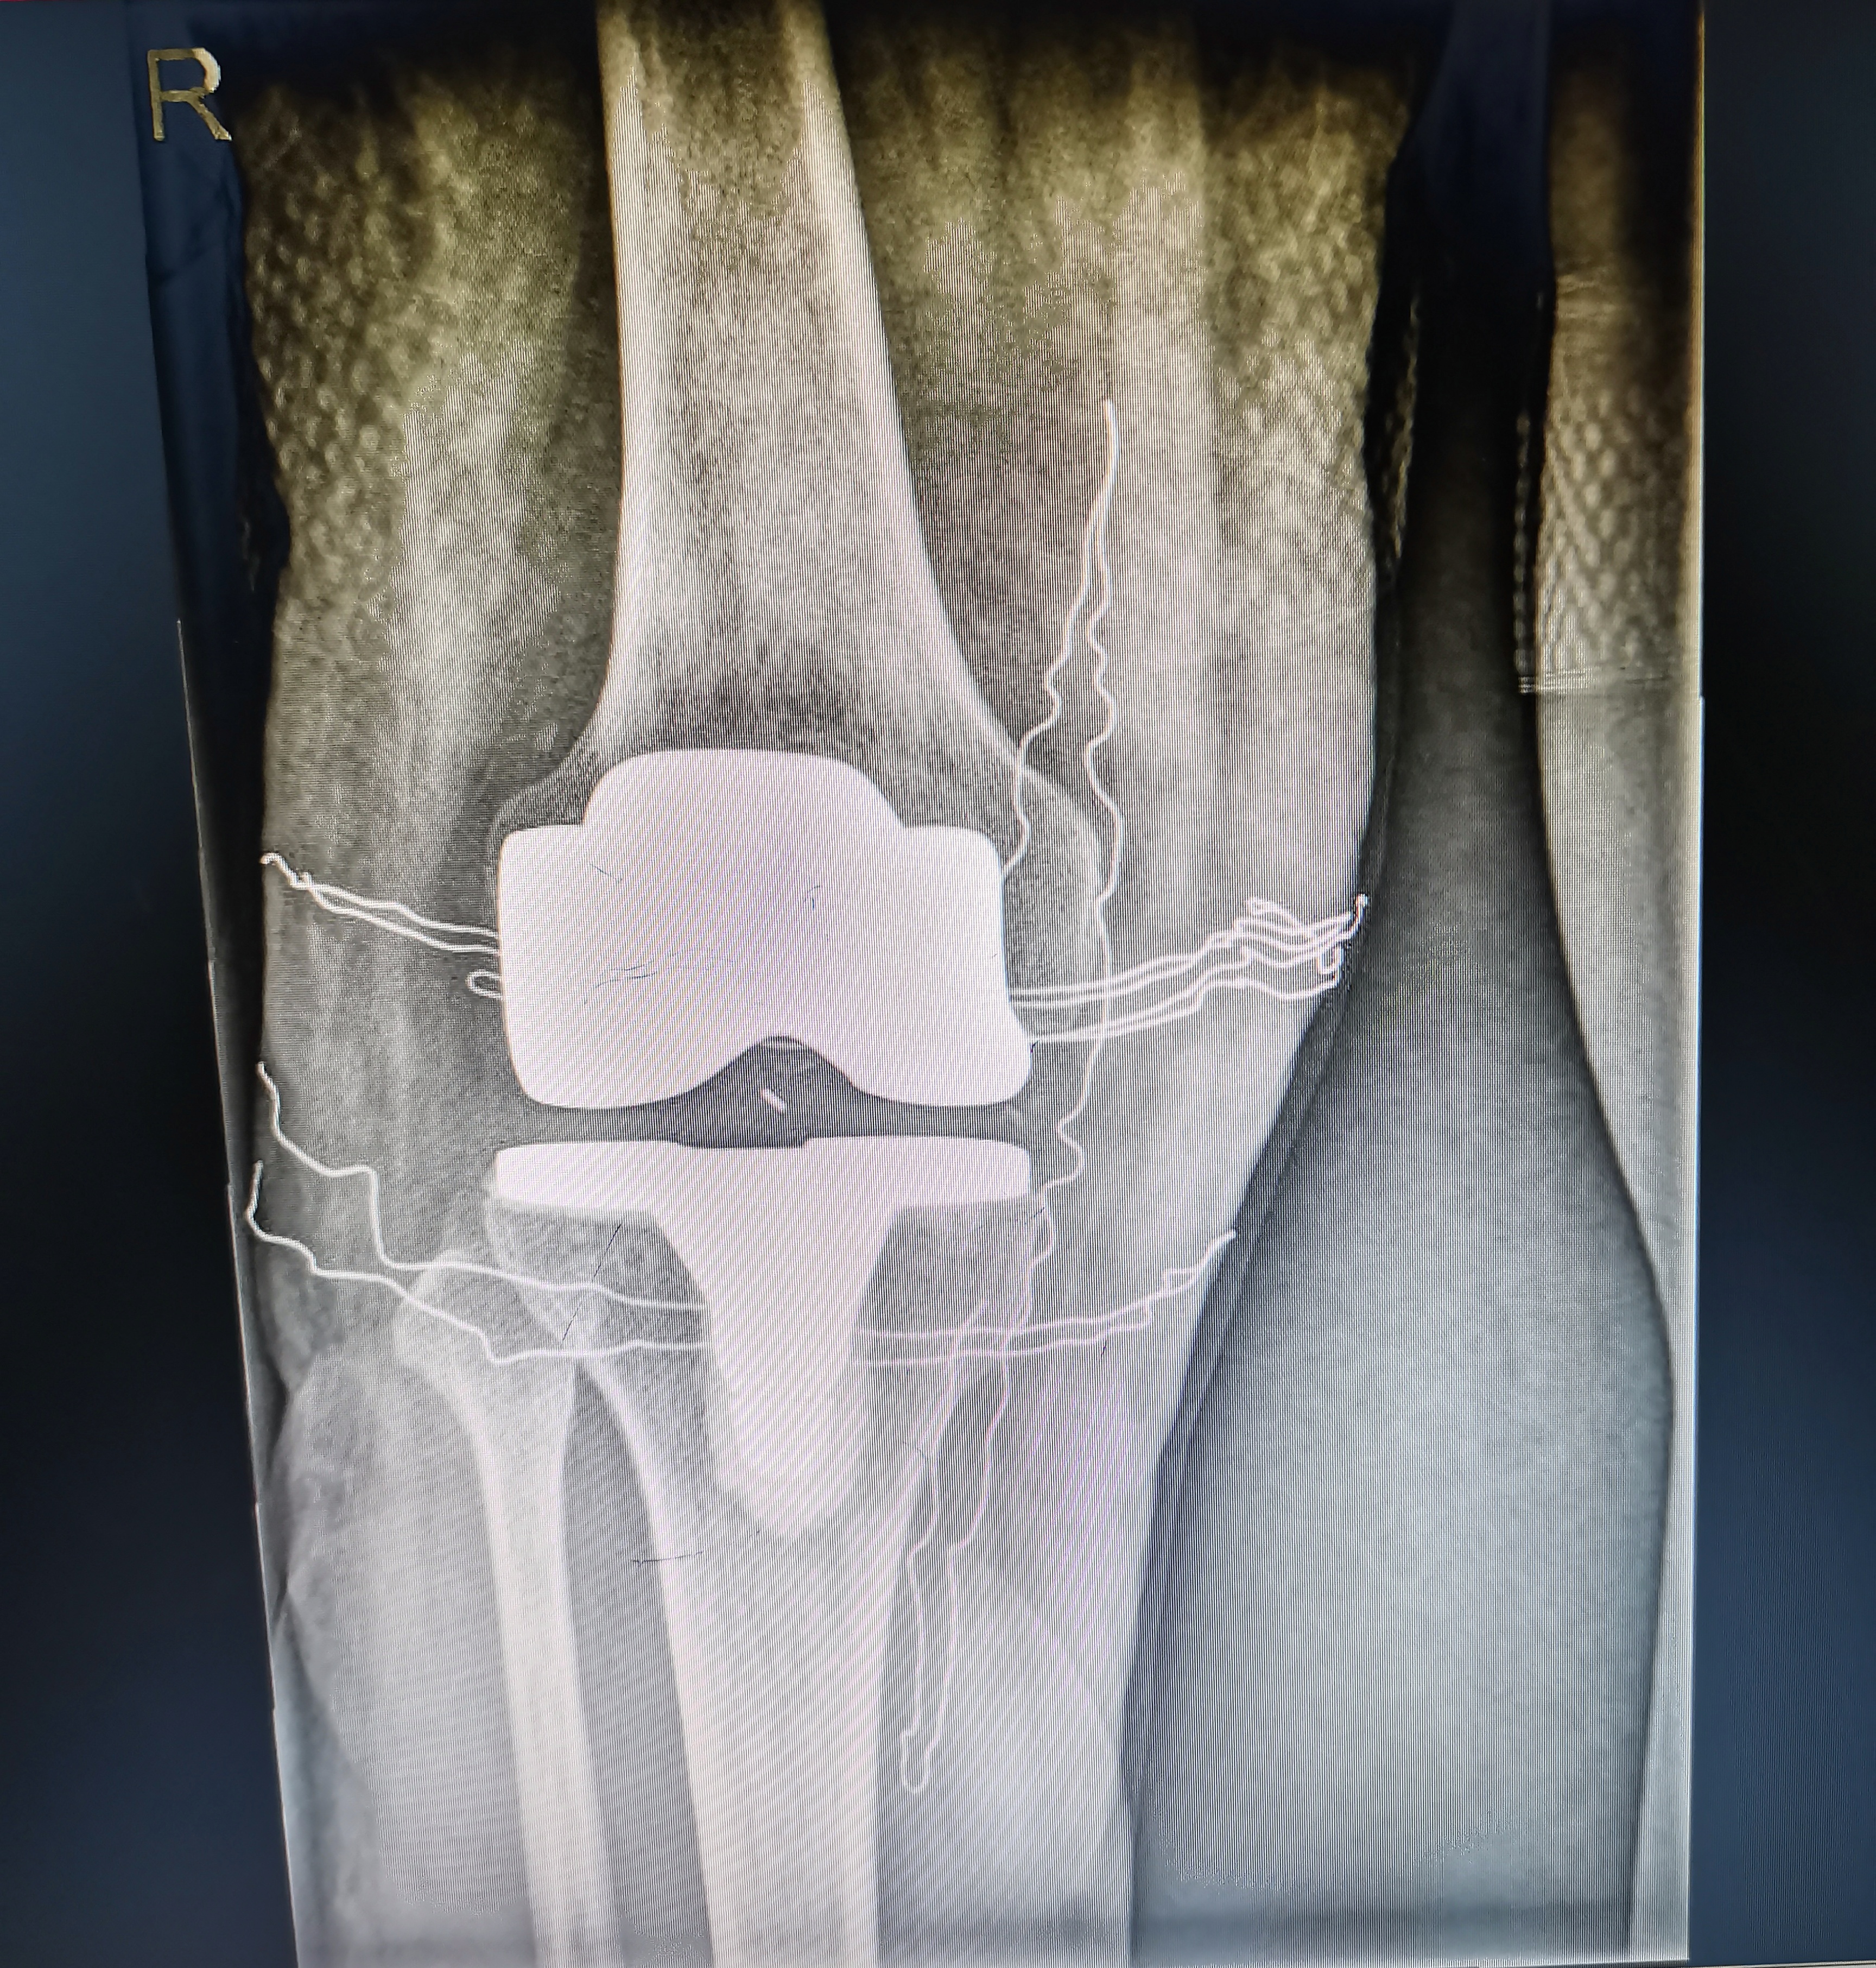

術(shù)中照片

術(shù)后照片